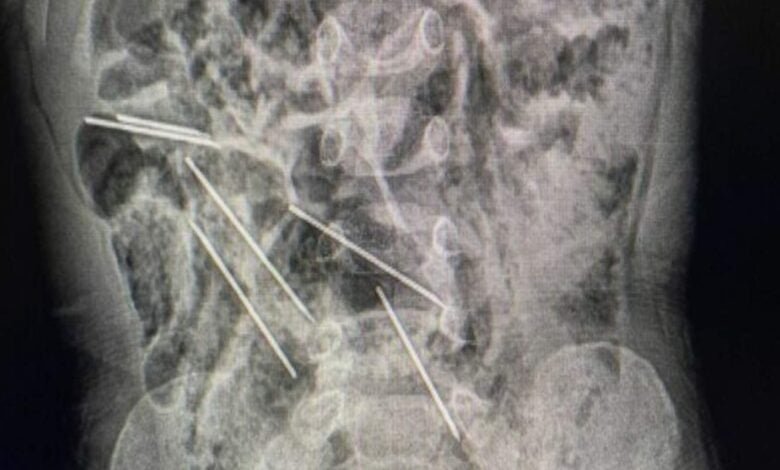

أنقذ الأطباء في شمال شرق بيرو طفل يبلغ من العمر عامين، بعد أن ابتلع ثماني إبر أثناء اللعب.

وقال الدكتور إفراين سالازار: “عندما كنا في غرفة العمليات وفتحنا بطنه، وجدنا تلك القطع المعدنية، وأدركنا أنها كانت في الحقيقة إبرًا”.

ويُذكر أن هذه الإبر هي لتطعيم حيوانات المزرعة حيث تعمل والدة الصبي.

وقالت الوالدة إنه ربما ابتلعها عندما كان يلعب هناك، علماً أن حالته الصحية أصبحت مستقرة بعد الجراحة.